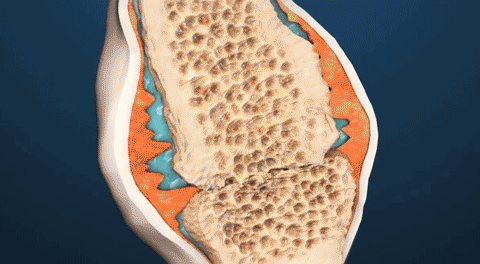

Comfrey gélben Nautubone serkenti a porcsejtek osztódását és akár hétszeresére növeli a kollagénszintézist a porcokban. A kondrociták a porcszövet alapvető sejtjei. Ezért minél több belőlük, annál erősebb a porc. vagyis Nautubone nadograđuje vezivna tkiva i popunjava prazninu u zglobnoj čahuri.

Comfrey gélben Nautubone Nautubone felépíti a kötőszöveteket és kitölti az ízületi tokban lévő rést.